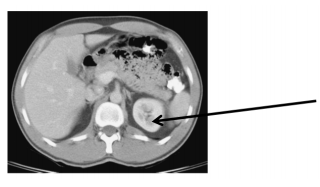

Qual é o ponto assinalado na imagem de tomografia a seguir?